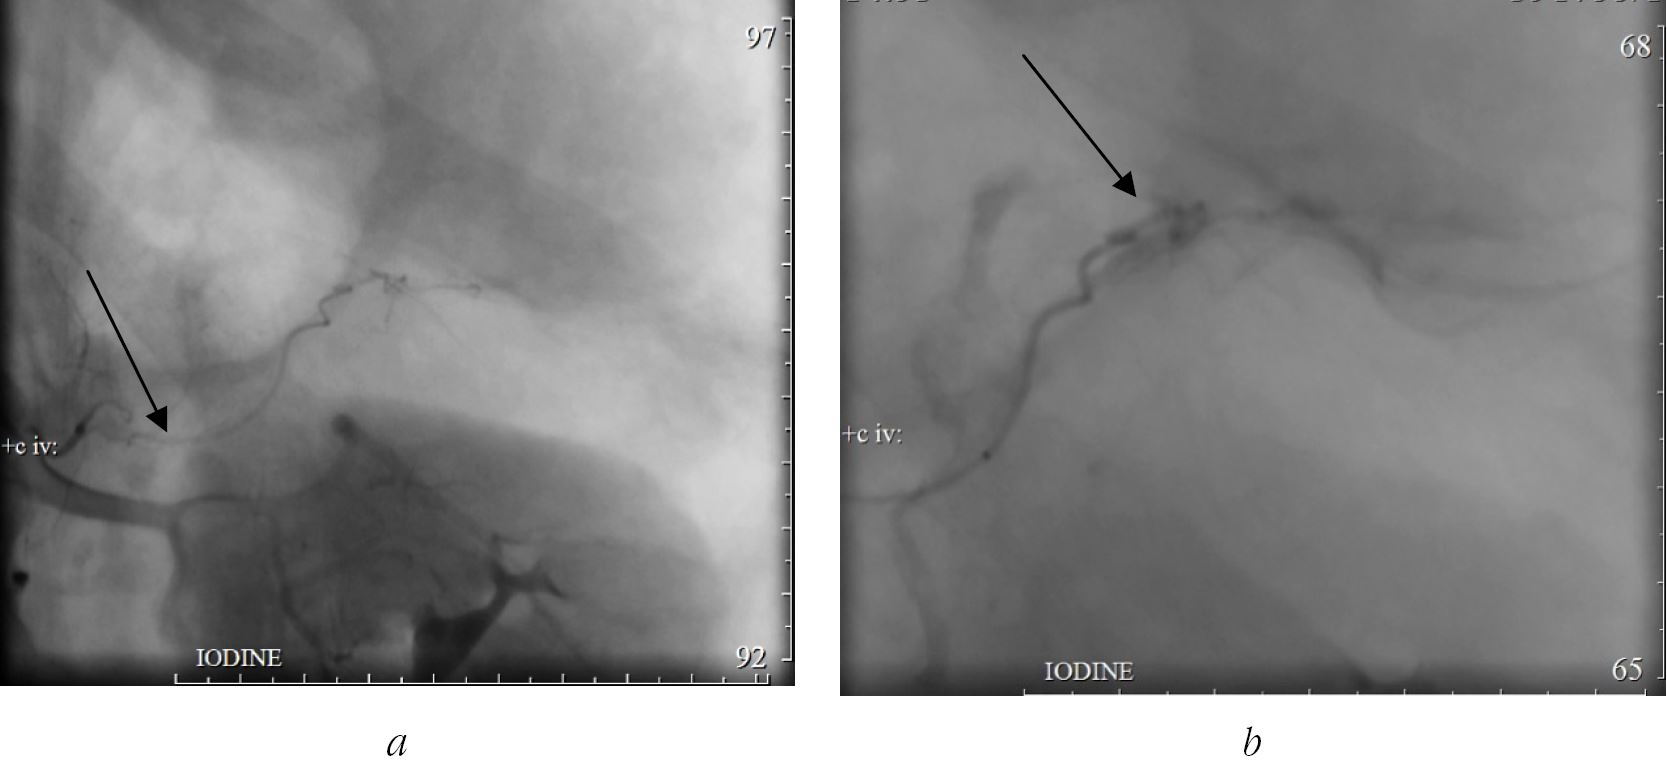

On the 30th day after surgery, there was a deterioration in the patient's condition. According to the complete blood test, hemoglobin levels decreased to 63 g/L, hematocrit to 17.9 %, red blood cells to 2.18·1012/L. To exclude repeated arrosive hemorrhage from the pancreas parenchyma, angiography was performed. The study revealed an aberrant branch of the celiac trunk that departed 0.3 cm above the left renal artery and hypervascularization in the spleen gate projection (in the area of the pancreatic tail pseudocyst). The hemorrhage was stopped by

X-ray endovascular embolization of the aberrant artery lumen using a Merit Maestro 2.4F microcatheter and ASAHI Fielder conductor with PVA particles (45–150 microns – Boston Scientific) (Fig. 3).

Fig. 3. X-ray endovascular embolization of the aberrant artery lumen: a – pathological branch of the splenic artery feeding the area of the formed pseudocyst; b – embolization of the artery with PVA particles